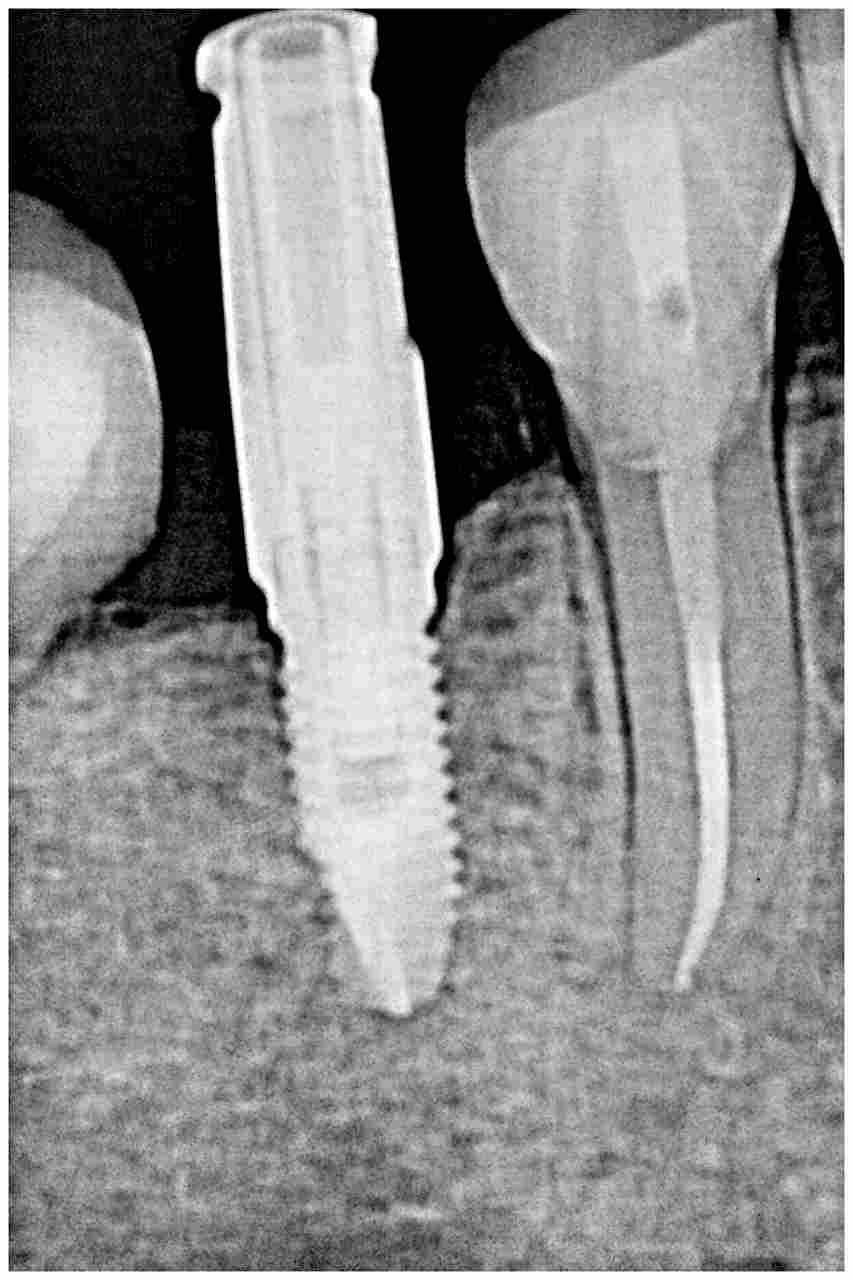

インプラント埋入をしていきます 4mmの11.5mmというインプラントを埋入していきました

インプラント埋入をしていきます 4mmの11.5mmというインプラントを埋入していきました

角度、方向、深度、埋入位置に注意を払っています

しっかりと骨内にインプラントが入りました